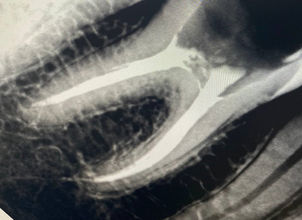

НАШІ КЕЙСИ